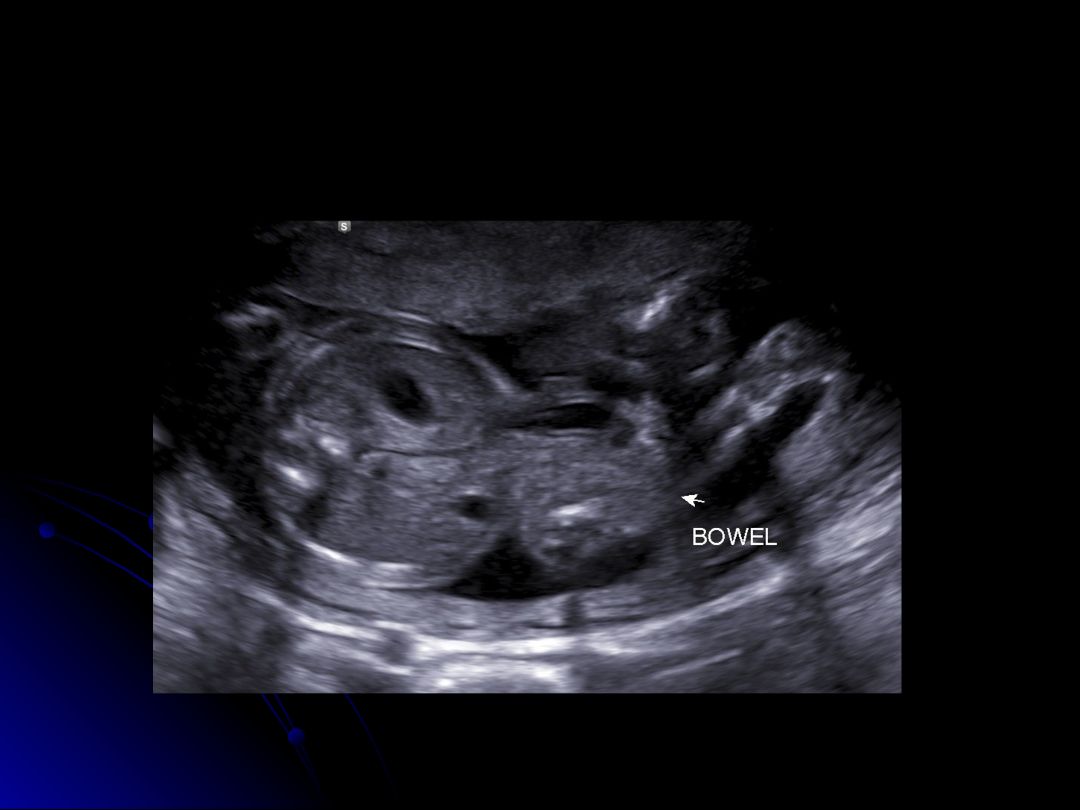

Which of the following conditions is characterized by the herniation of bowel loops outside the fetal abdomen without a covering membrane?

Gastroschisis